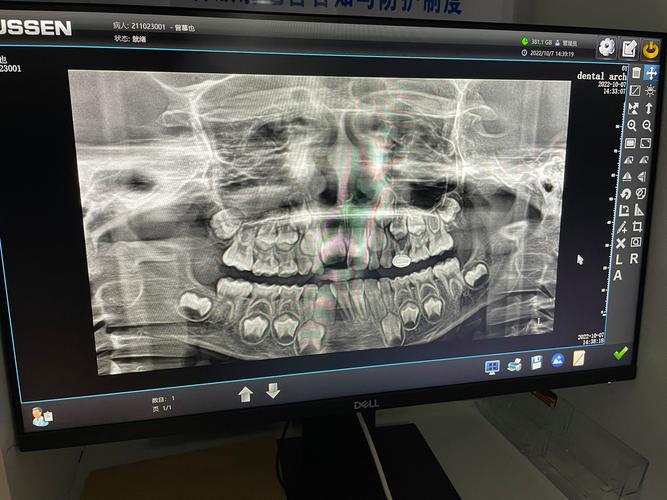

八岁的孩子通常处于混合牙列中期,第一恒磨牙(俗称“六龄齿”)已经萌出,上下颌前牙也可能开始替换,颌骨仍处于快速发育阶段,上颌骨的腭中缝(左右上颌骨之间的连接处)尚未完全闭合,这意味着通过外力引导,牙弓的宽度可以被有效扩大,相比青春期或成年后,八岁儿童的扩弓效率更高、复发风险更低,甚至能避免后期复杂的正畸治疗,若孩子存在后牙反颌(即“地包天”的一种表现,下后牙咬合在上后牙外侧),扩弓不仅能纠正咬合关系,还能刺激上颌骨正常发育,改善面部侧貌;若牙弓狭窄导致恒牙萌出空间不足,提前扩弓能为恒牙预留“位置”,减少将来拔牙的可能性。

并非所有八岁孩子都需要扩弓,医生通常会根据临床检查和影像学结果判断,常见的适应症包括:

- 后牙反颌:表现为一侧或双侧下后牙咬合在上后牙外侧,可能影响咀嚼功能,甚至导致面部不对称。

- 牙弓狭窄:上颌牙弓宽度不足,前牙拥挤或“龅牙”倾向,恒牙萌出时位置不够。

- 上颌发育不足:上颌骨整体偏小,除了牙弓窄,还可能伴随鼻基底部凹陷、面中份发育不足等问题。